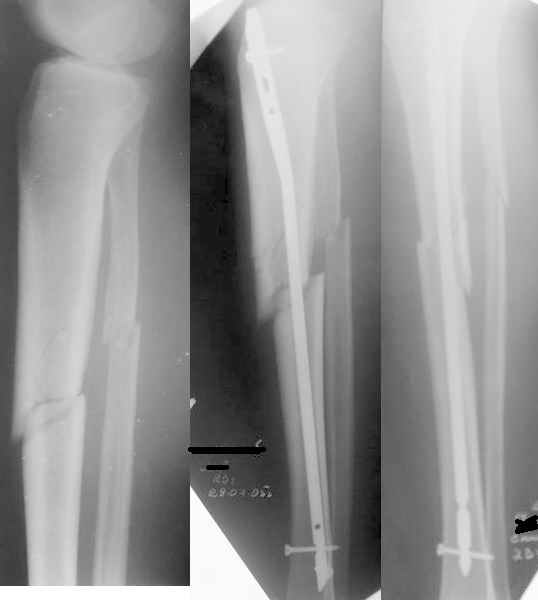

Уважаемые коллеги. Подскажите, где допущена ошибка и как её исправить. Пациент 23 лет. Травма 24.07.05 спрыгнул с высоты 1,5 метров. До операции гипсовая иммобилизация. 29.07 закрытая репозиция и интрамедуллярный блокированный синтез штифтом "Остеомед". Подскажите, где допущена ошибка, приведшая к смещению и как её исправить. С уважением, Александр Шевченко

Более красивую рентгенограмму позволилО бы получить:

1)предварительное восстановление длины голени с помощью того или иного вытяжения (основная проблема в этом случае).

2) п.1 + введение в центральный отломок во фронтальной плоскости отклоняющего (poller) винта или спицы кзади от желаемой траектории гвоздя.

3)п.1 + использование стержня большего диаметра (этот 8 мм тут как карандаш в стакане).

Беда, в общем, небольшая. По-научному говоря, может (и должно) "захрястнуть" и так.

Разрешите полюбопытствовать - почему в центральный отломок ввели единственный винт, но в 45-градусное отверстие?

Вы выбрали штифт малого диаметра. Был бы он потолще, то все бы встало на свои места.

Коррегировать я бы не стал. В одной плоскости выглядит добольно таки прилично, большого укорочения нет. Через 6 недель я бы удалил проксимальный шуруп.

1. X ray snimki ne sovsem xoroshie: xotelos' bi uvidet' AP proximal'noii tibii.

2. V liubom sluchaie Nail ( gvozd'),slishkom malogo diametra, i korotkii, chto i iaviloc' prichenoi

malalignmnt.

Zamenite na bol'shii diametor i dlinee.